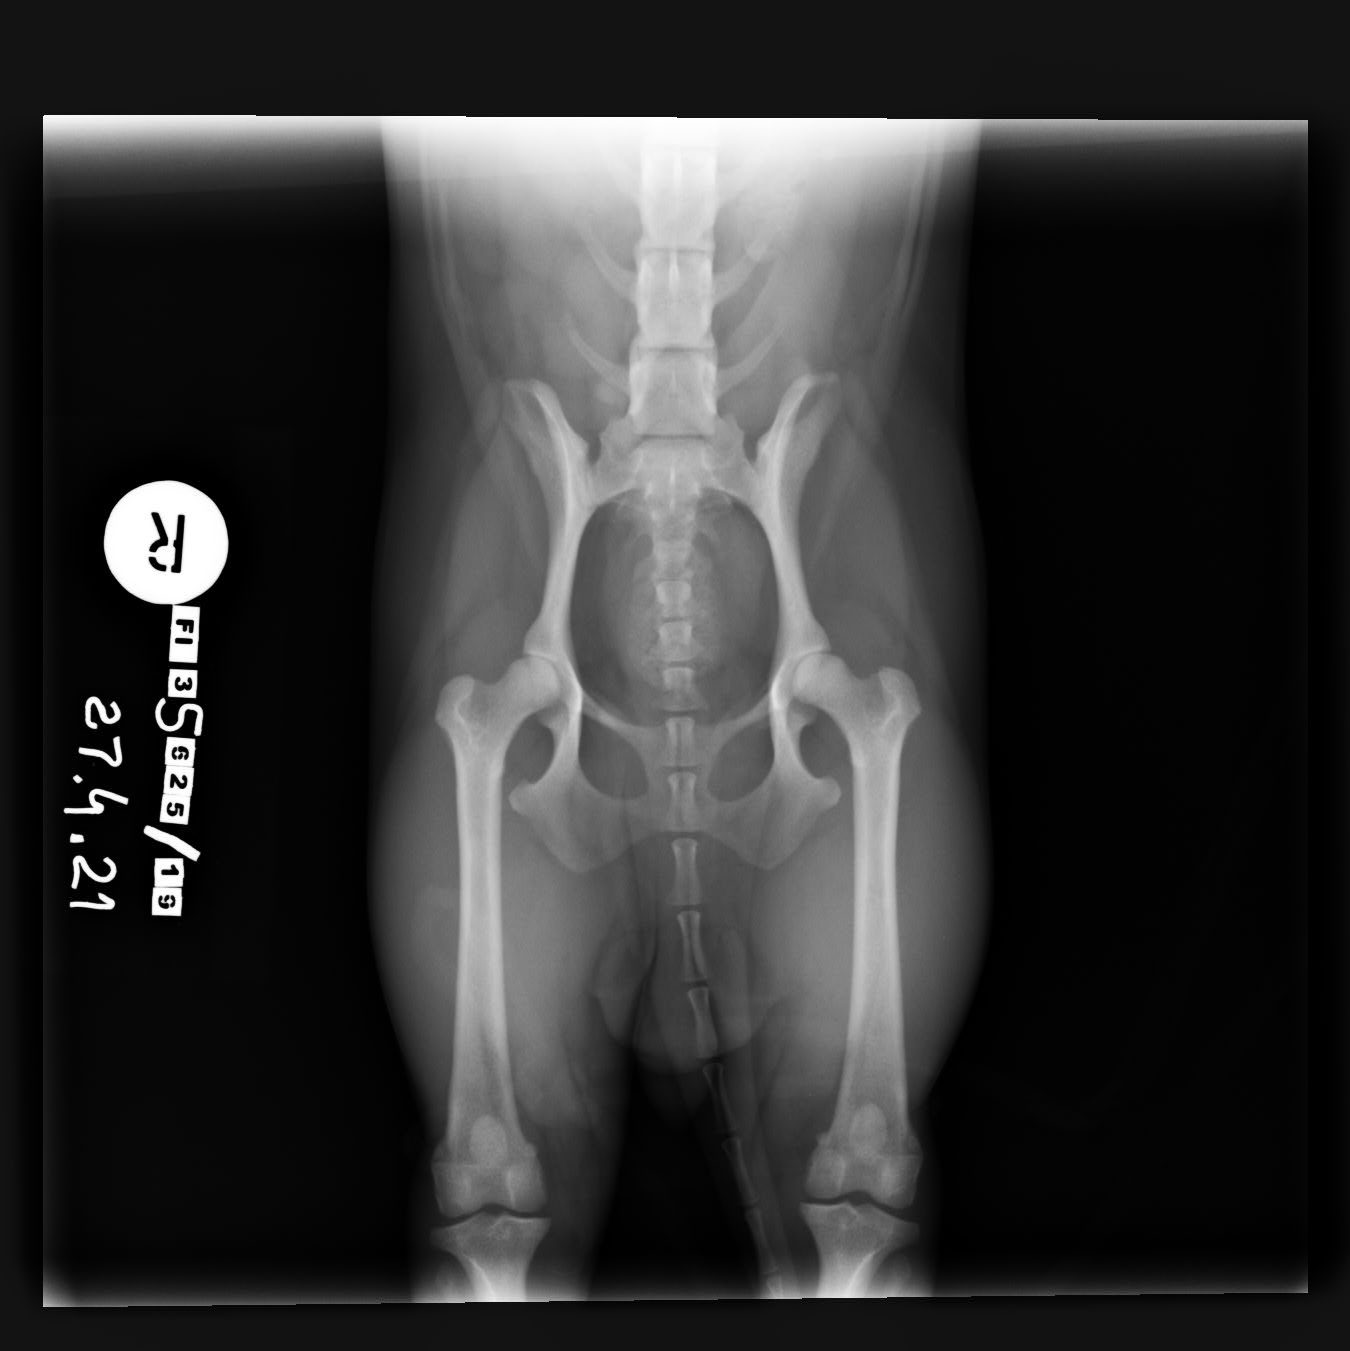

Lonkkaniveldysplasia

Lonkkanivelen kasvuhäiriö on yleisimpiä luustoon liittyviä sairauksia koirilla.

Koiran lonkkaniveldysplasian vakavuusaste määritellään lonkkien röntgenkuvista, joissa arvioidaan reisiluun pään ja lonkkamaljan yhteensopivuutta. Yhteensopivuus ilmoitetaan asteikolla A-E, jossa:

- A = normaalit lonkkanivelet

- B = lähes normaalit lonkkanivelet

- C = lonkissa on lievä dysplasia

- D = lonkissa on kohtalaisia muutoksia

- E = lonkat ovat vaikeasti dysplastiset, jolloin pahimmillaan reisiluun pää ei pysy lonkkamaljassa lainkaan.

Lonkkakuvauksen alaikäraja on 12 kk.